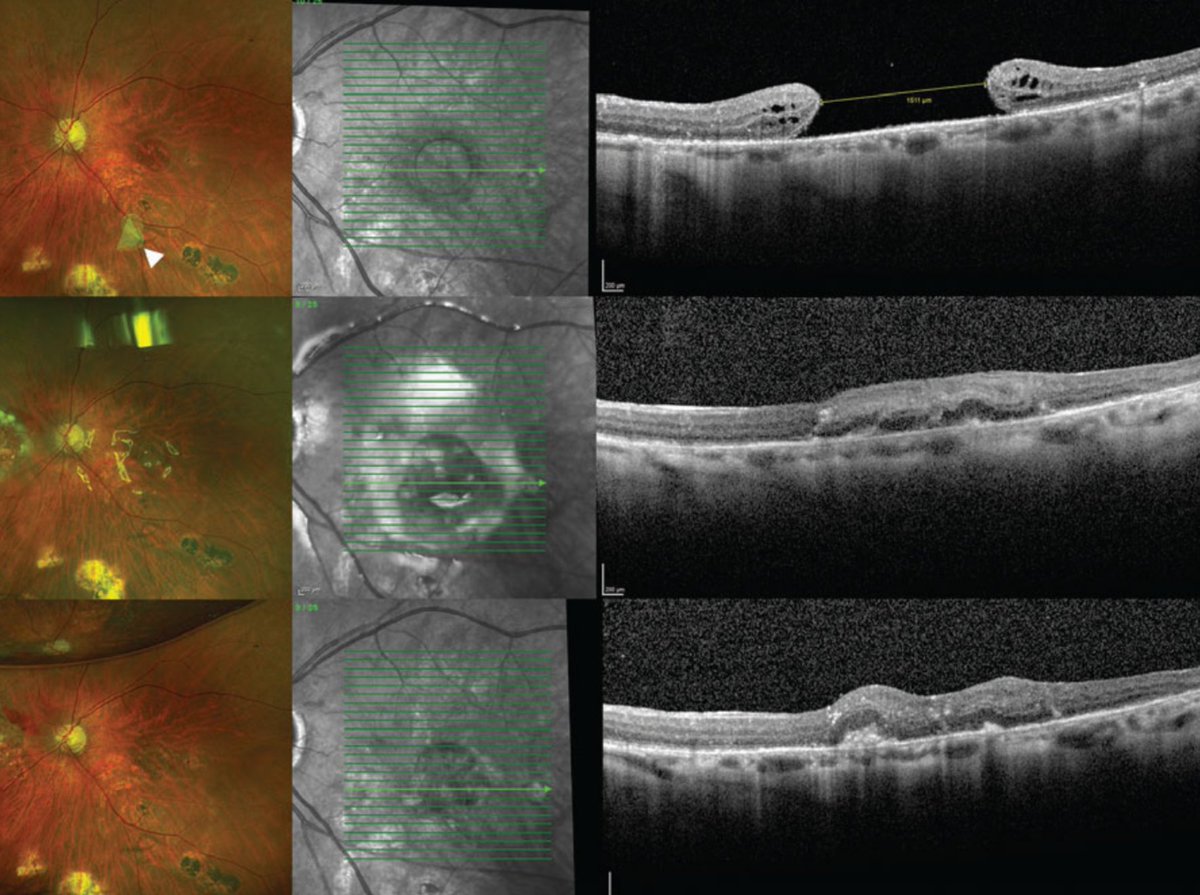

Autologous retinal transplantation is one surgical technique showing promise for large or recurrent macular holes, especially those >800 µm.